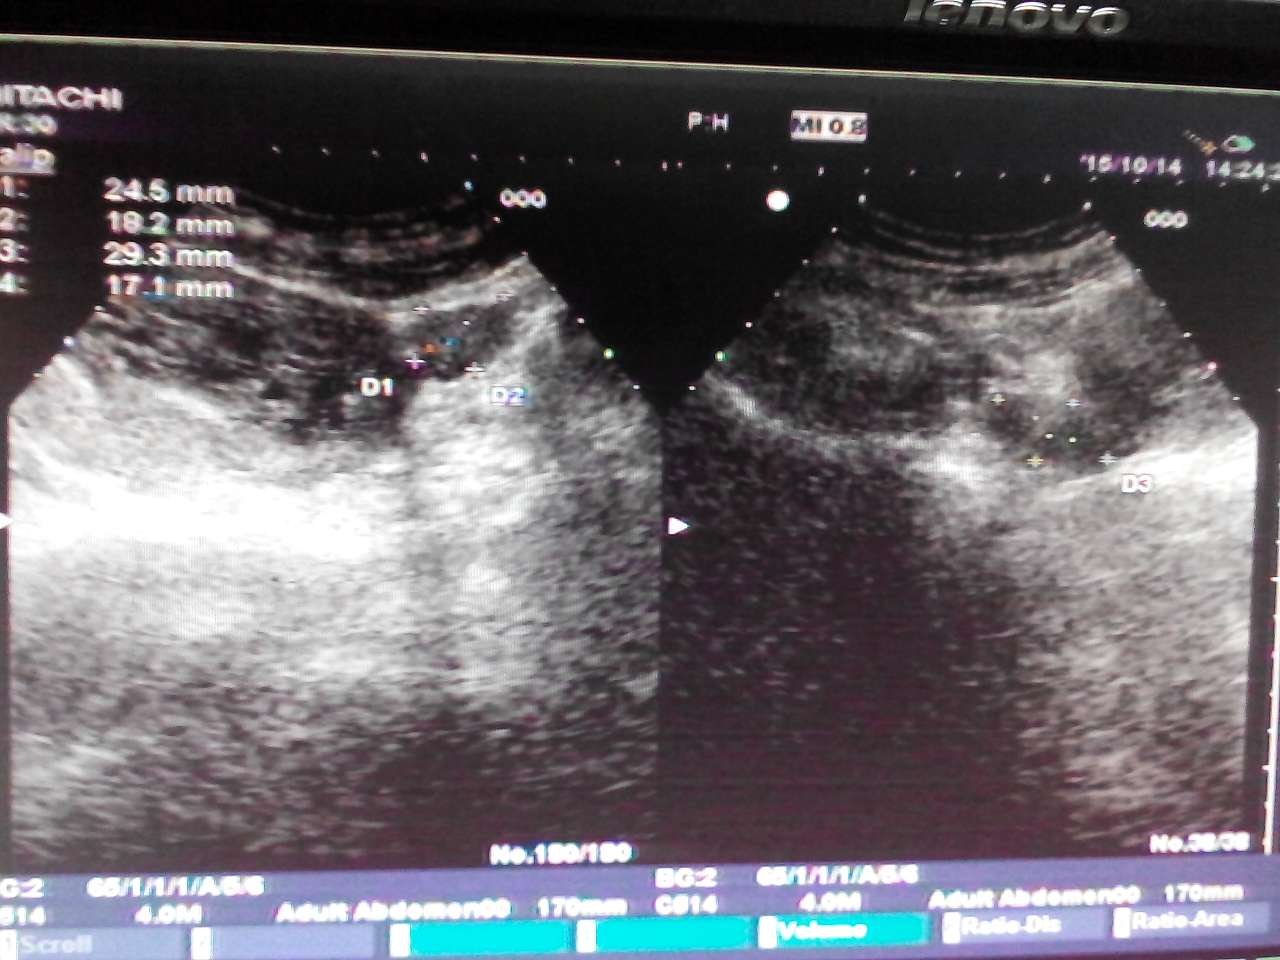

葡萄胎 ( Hydatidiform mole )

别名: 水泡状胎块